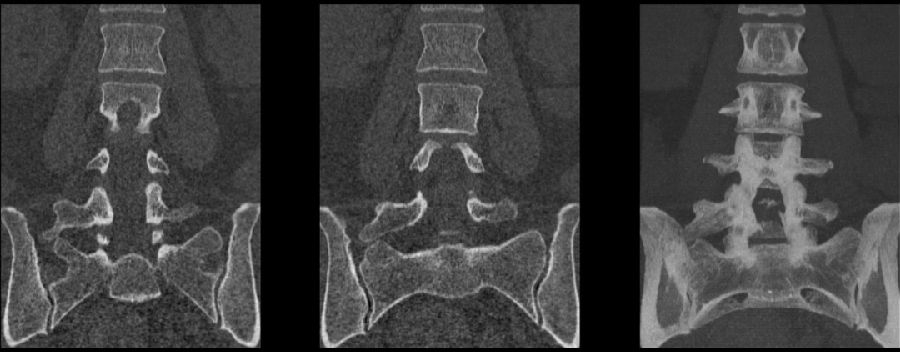

II型:表现为不完全的腰椎骶化,具有增宽的横突,并且和骶骨形成假关节,并将其分为两个亚型IIa(单侧关节形成)或IIb(双侧关节形成)

L5左侧横突肥大,假关节形成,为Ⅱa型

L5双侧横突肥大,假关节形成,为Ⅱb型

III型:单侧(IIIa)或双侧(IIIb)腰椎完全骶化,腰5横突与骶骨完全骨性融合

L5右侧横突肥大与骶骨发生骨性融合,为Ⅲa型

L5双侧横突与骶骨骨性融合,为Ⅲb型